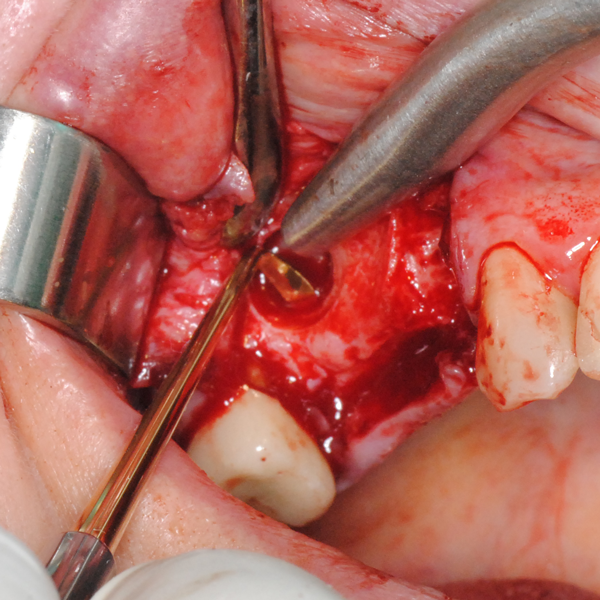

Отворен максиларен синус в началото на интервенцията. Случаят е интересен със следното - твърде атипична форма на трепанационния отвор. На какво се дължи на това - на лошо планиране на оперативния достъп или на нещо друго? Дължи се на факта, че отначало въпросната намеса беше планирана като балонен синуслифт; за съжаление обаче мембраната на синуса се разкъса и надуването на балона стана невъзможно.